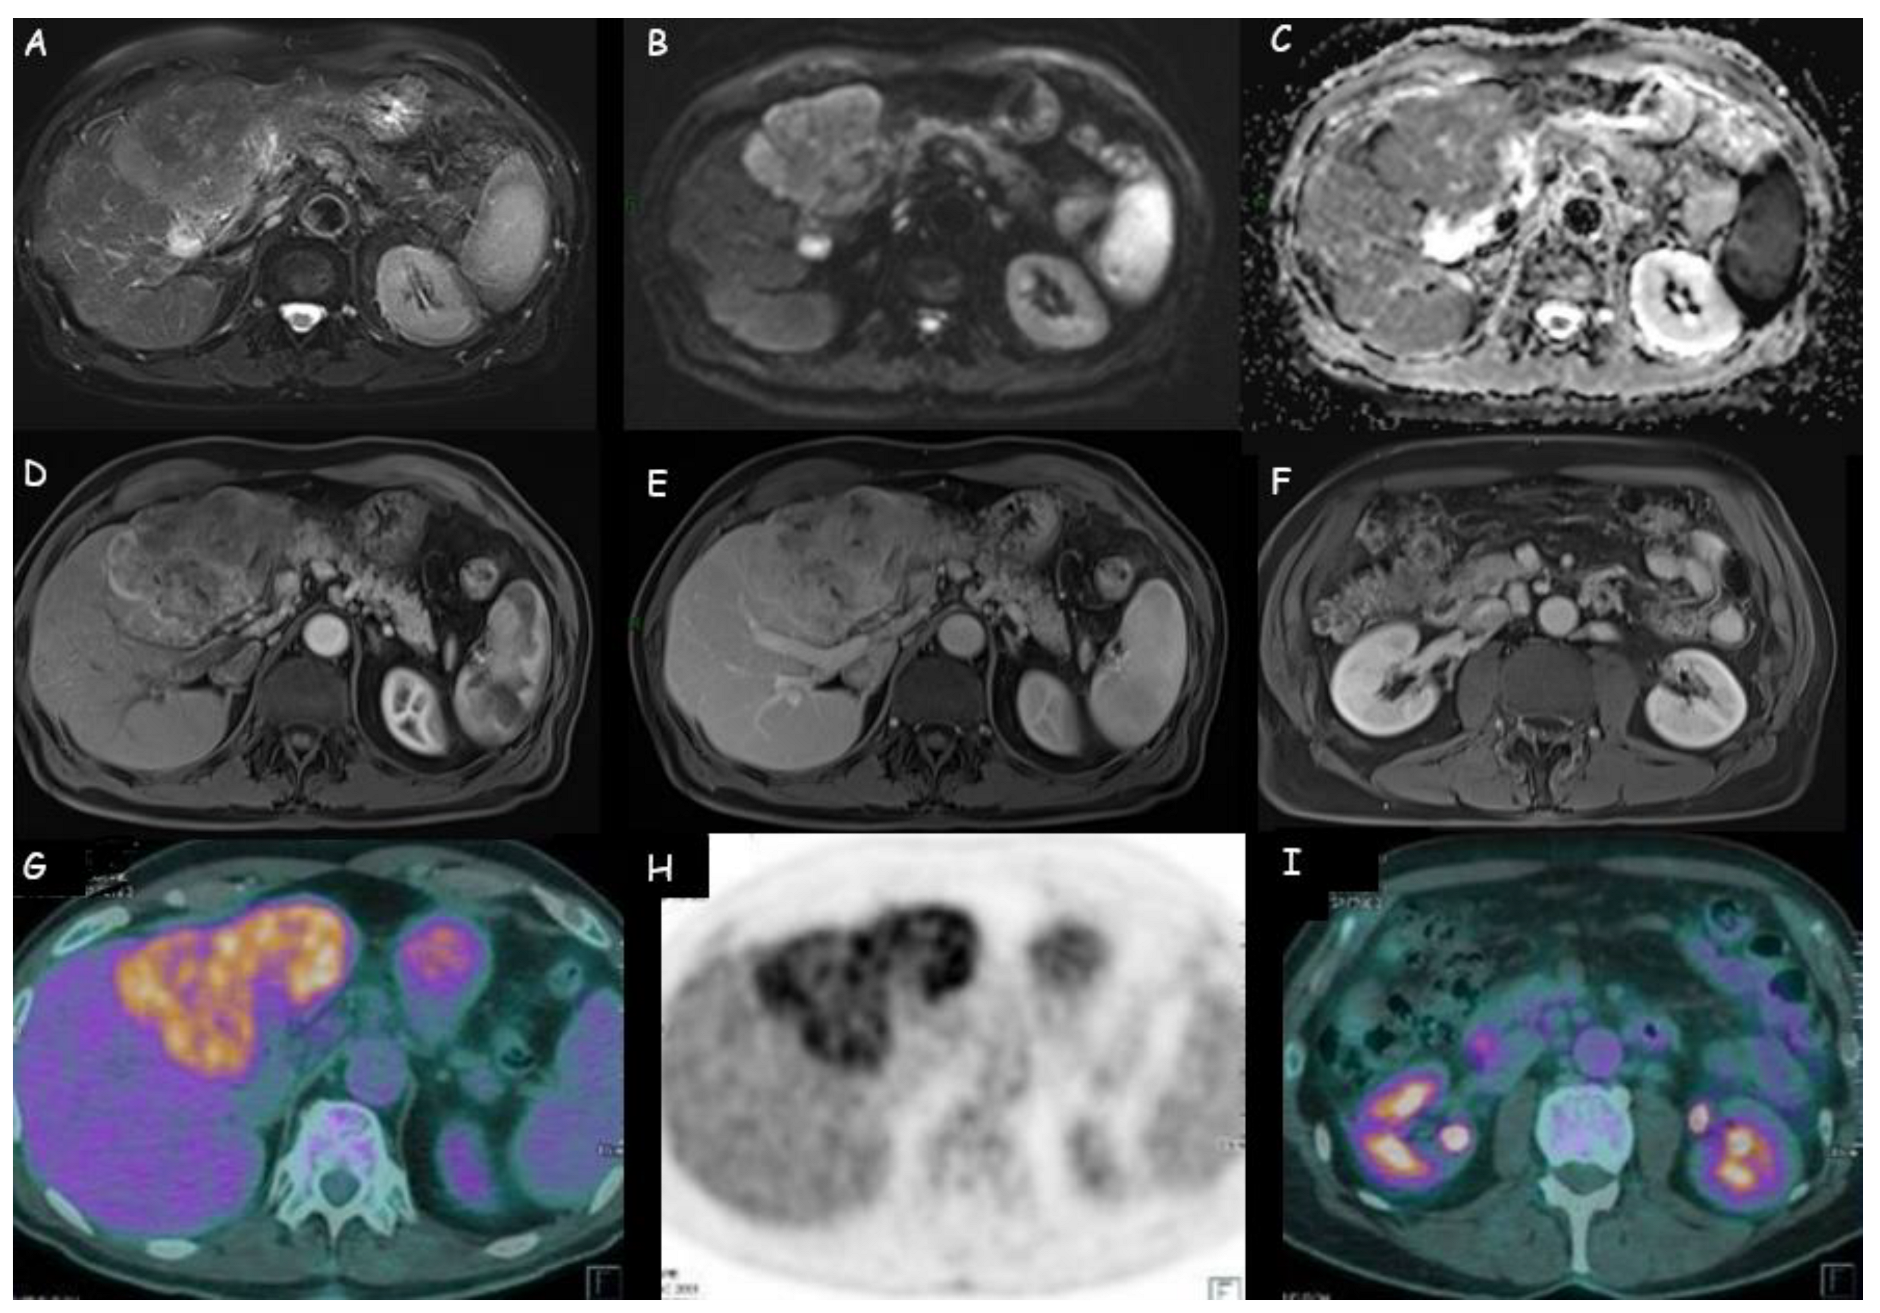

1.3. Positron Emission Tomography with Fluorodeoxyglucose

- Huang, X.; Yang, J.; Li, J.; Xiong, Y. Comparison of magnetic resonance imaging and 18-fludeoxyglucose positron emission tomography/computed tomography in the diagnostic accuracy of staging in patients with cholangiocarcinoma: A Meta-Analysis. Medicine 2020, 99, e20932. [Google Scholar] [CrossRef]

- Jiang, L.; Tan, H.; Panje, C.M.; Yu, H.; Xiu, Y.; Shi, H. Role of 18F-FDG PET/CT Imaging in Intrahepatic Cholangiocarcinoma. Clin. Nucl. Med. 2016, 41, 1–7. [Google Scholar] [CrossRef] [PubMed]

- Fiz, F.; Masci, C.; Costa, G.; Sollini, M.; Chiti, A.; Ieva, F.; Torzilli, G.; Viganò, L. PET/CT-based radiomics of mass-forming intrahepatic cholangiocarcinoma improves prediction of pathology data and survival. Eur. J. Nucl. Med. Mol. Imaging 2022, 49, 3387–3400. [Google Scholar] [CrossRef] [PubMed]

- Jiang, C.; Zhao, L.; Xin, B.; Ma, G.; Wang, X.; Song, S. 18F-FDG PET/CT radiomic analysis for classifying and predicting microvascular invasion in hepatocellular carcinoma and intrahepatic cholangiocarcinoma. Quant. Imaging Med. Surg. 2022, 12, 4135–4150. [Google Scholar] [CrossRef] [PubMed]